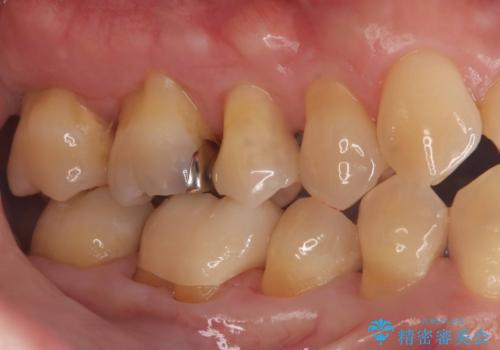

- 「銀歯を白くしたい」を主訴に来院された患者様です。銀歯を外し虫歯を除去後、オールセラミッククラウンで治療を行いました。

銀歯を外して内部の虫歯を丁寧に除去した後、オールセラミッククラウンにて修復を行いました。審美性と機能性の両面で改善が得られ、患者様にもご満足いただきました。